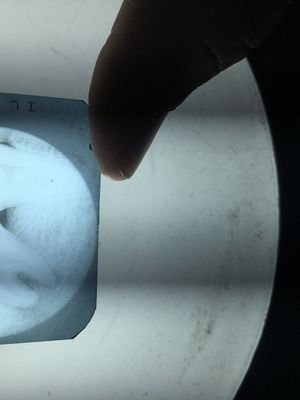

My friend had tooth ache with pain of last 6months ago he consult a dentist, so dentist suggested that to have a filling . so my friend made permanent filling after this he is ok but for now recently a month ago he had lost his filling and the some of the layer . this is the X-raywhich I have shown up...so what is the present situation of the tooth ?? & what is the diagnosis to be done further??? Either the tooth to be filled again or it should be extract ???

Dental Caries with perapical abscess. In my opinion, extraction is the ideal treatment in this case as its a third molar) Root canal Treatment would be another option. But i am skeptical about the scope of post-endodontic restoration!